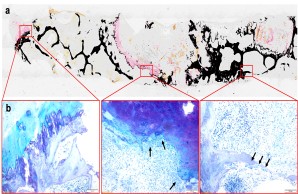

Fig.: Radiological (µCT; a) and histological (b) imaging of joint changes in post-traumatic osteoarthritis. The classic signs of osteoarthritis appear with osteophytes (blue arrows), meniscal degeneration (black arrow), joint deformation (dashed line), and loss of articular cartilage (red arrows).

Fig.: Nondecalcified histologic workup of bacterial inflammation of the intervertebral disc with osseous infiltration of the vertebral body. (a) Von Kossa/van Gieson overview staining. (b) Detailed images in toluidine blue staining. Arrows show highly activated osteoclasts responsible for vertebral bone destruction. Joint project with Orthopedics (PD Dr. Dr. Tim Rolvien), IOBM (Prof. Dr. Michael Amling) and Microbiology (Prof. Dr. Holger Rohde).